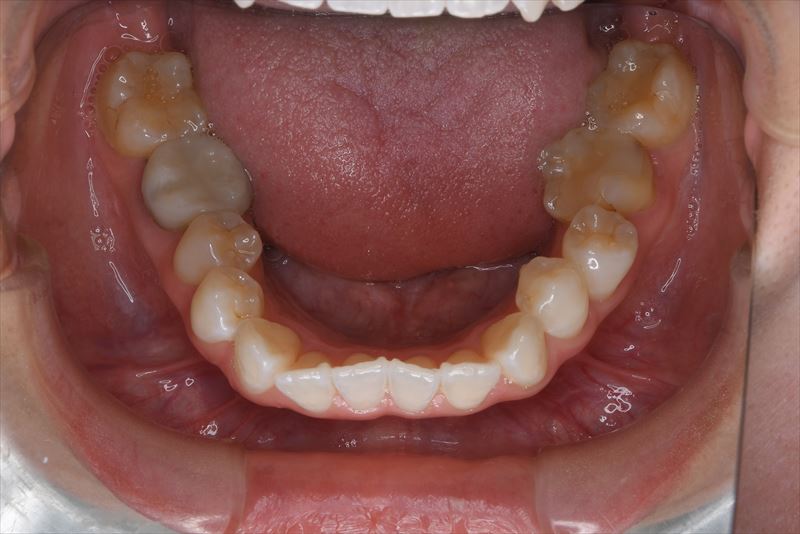

治療前

- 両側2番クロスバイト、叢生、上顎左側6番根尖病巣

- 上顎左側6番は失活歯で根尖病巣を認めたため抜歯し、上顎左側8番を代わりに使用することとしました。アンカースクリューを使用することにより、健康な歯を抜歯せず臼歯の遠心移動で叢生の改善できました。治療期間が短かく良好な咬合を獲得できました。